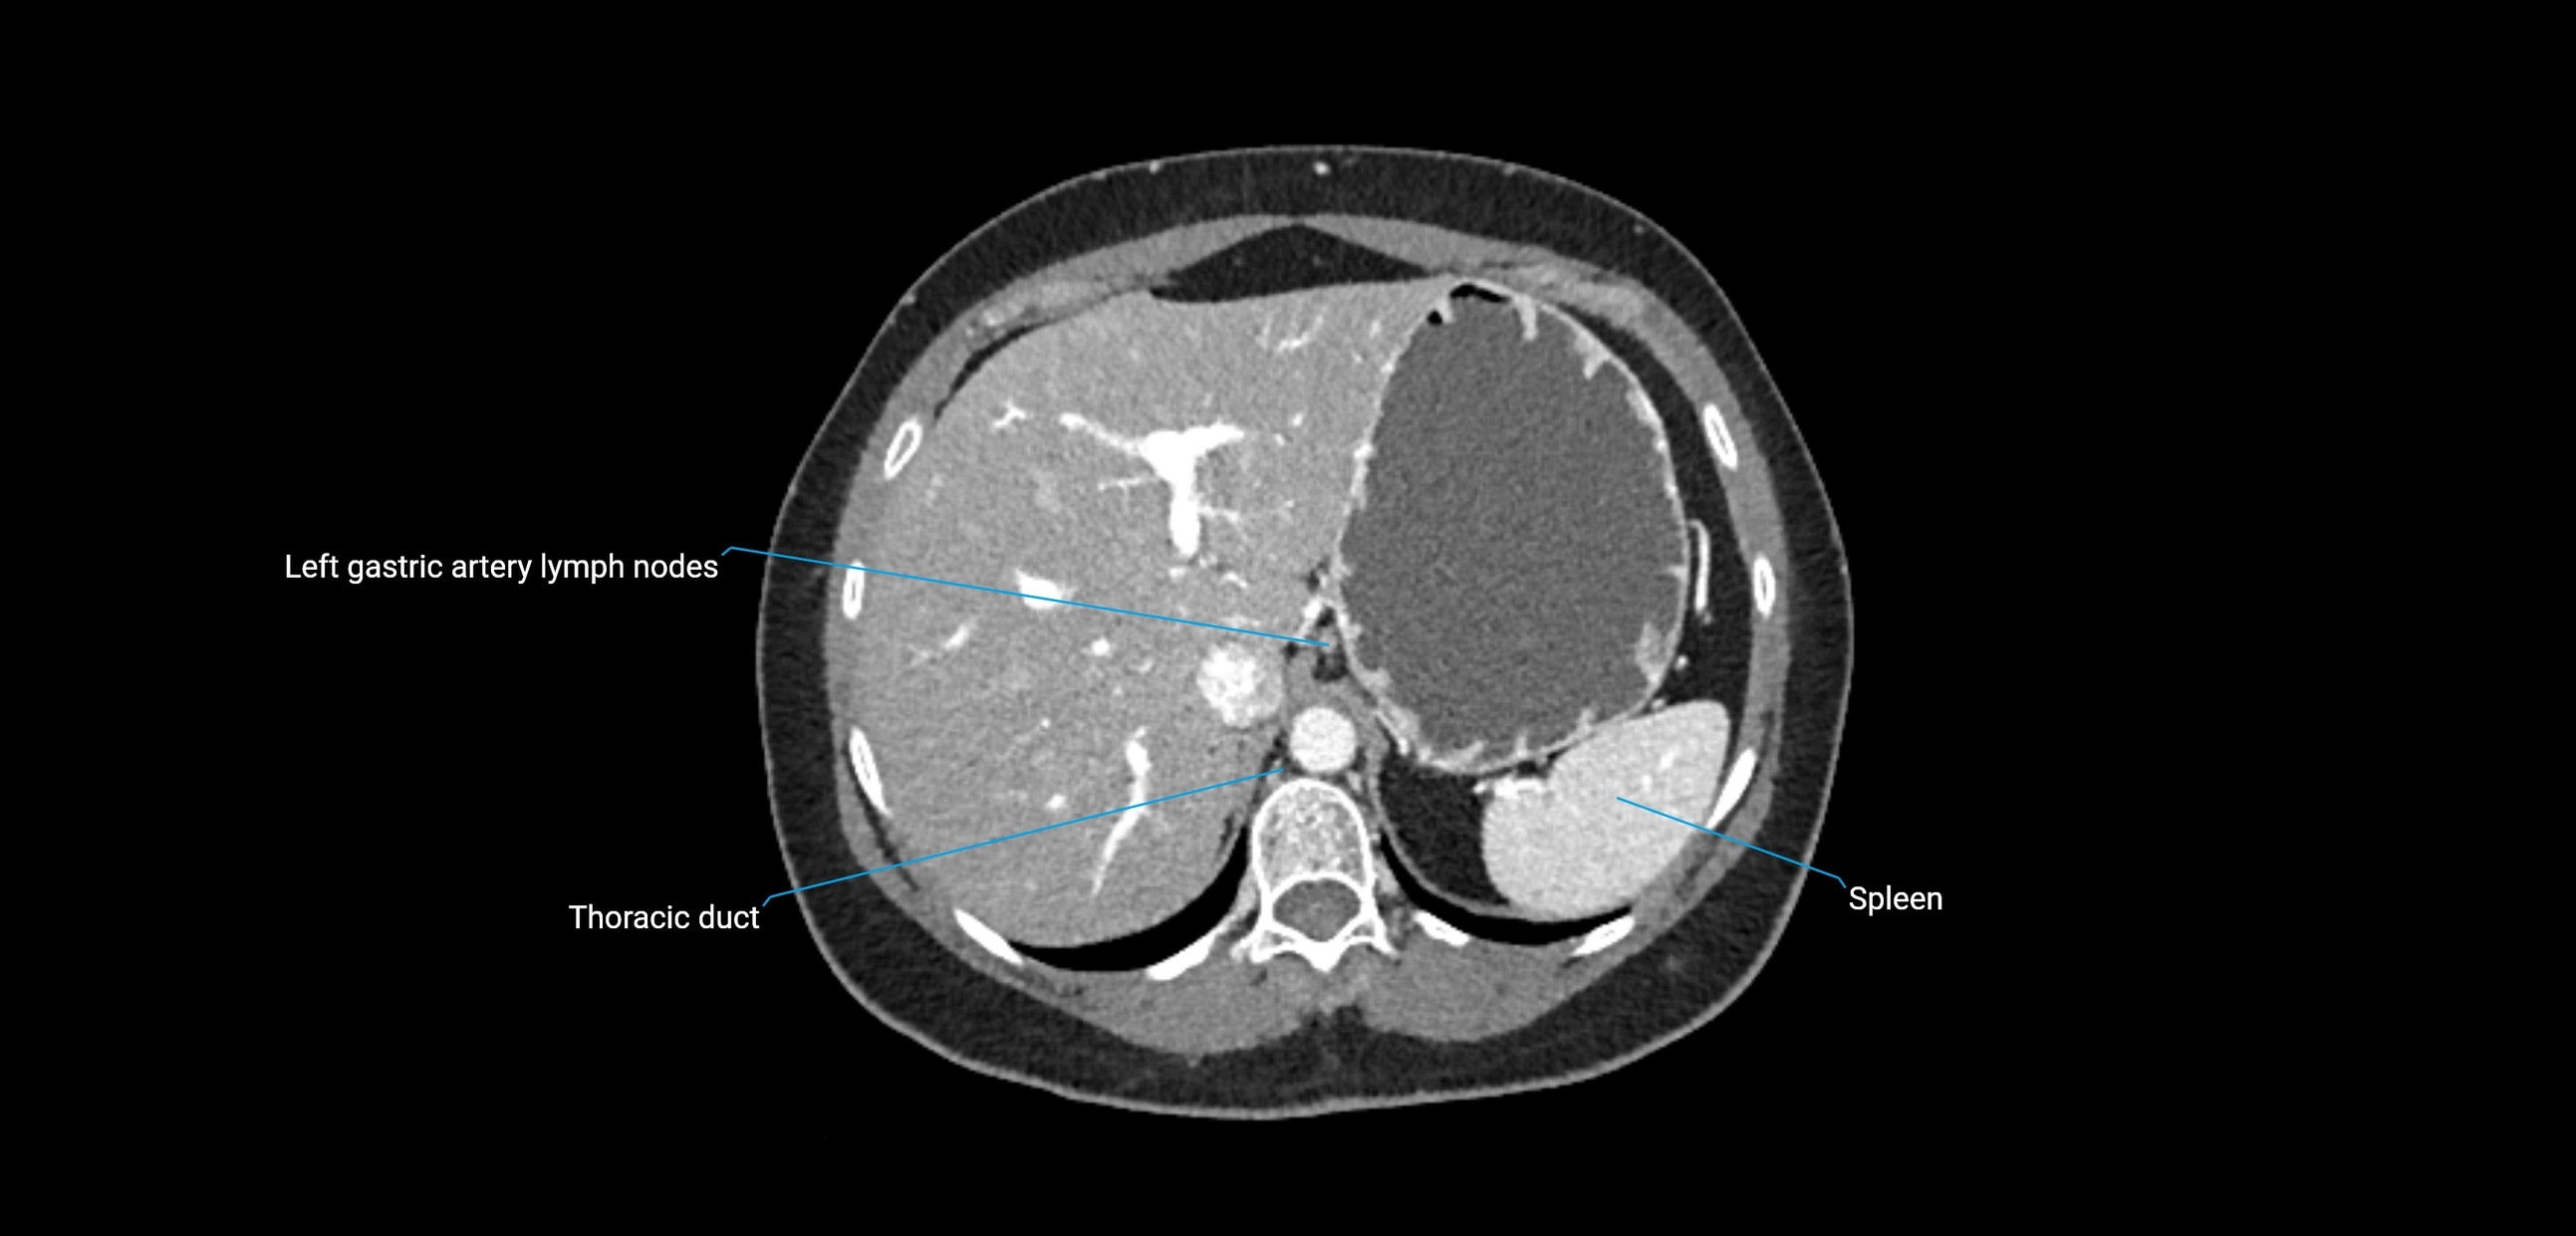

CT Appearance

CT Post-Contrast:

• Normal nodes enhance homogeneously

• Malignant nodes may show heterogeneous enhancement, central necrosis, or conglomerate formation

• Size >1 cm short axis is suspicious, though morphology and distribution are equally important